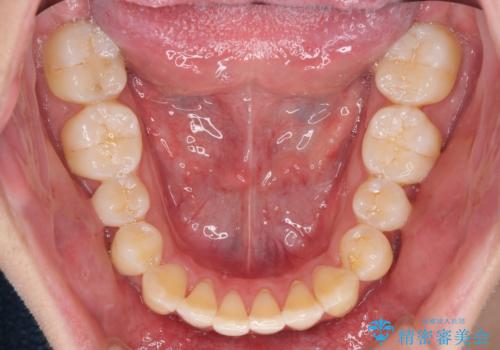

全体的に軽微な叢生が認められ、口元もやや前方に突出していたため、インビザラインでのIPR(歯と歯の間を削る)と歯列全体の後方移動によって歯並びを整えることとしました。

上下ともに歯列の幅が狭かったため、側方に拡大することで前歯のデコボコや突出感を解消するためのスペースを獲得することができました。

歯並びが改善したことはもちろん、咬み合わせの改善まで実感することができ、患者様には大変満足していただけました。